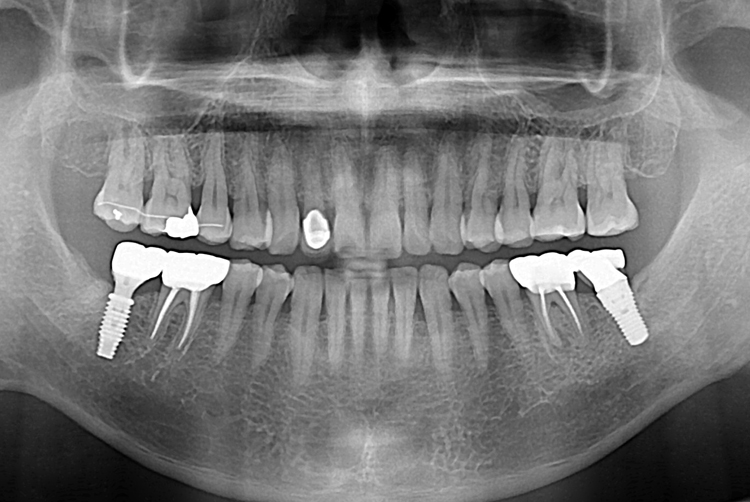

[임플란트] 어금니 임플란트

치료전 : 2018-06-26